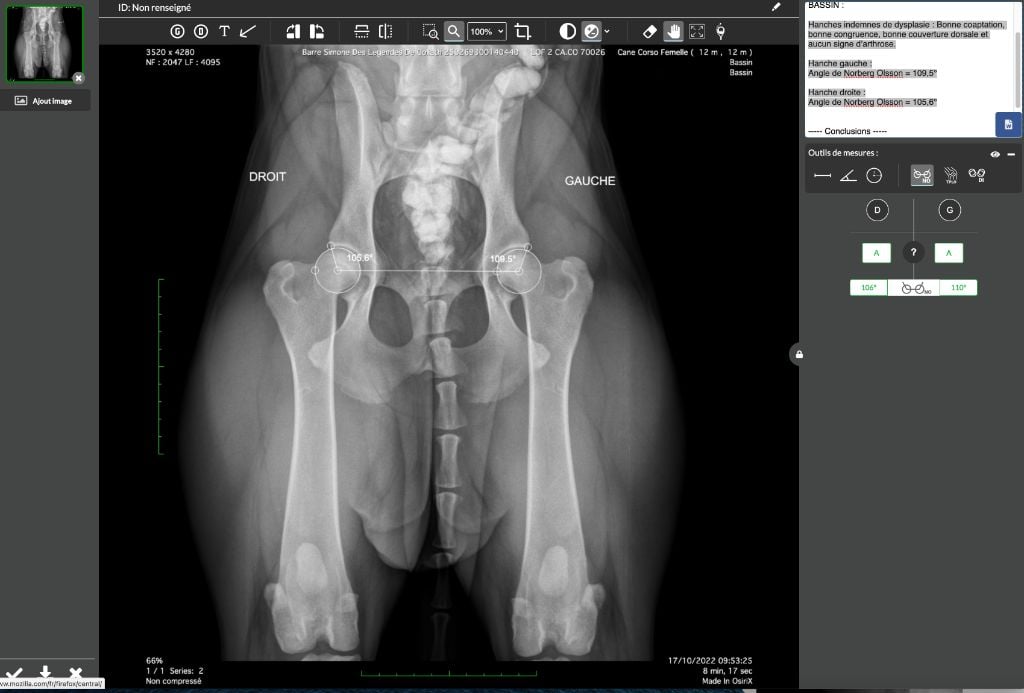

| Couleur | GRIS BRINGE DRSA N/N HD A / ED 0 officiel |